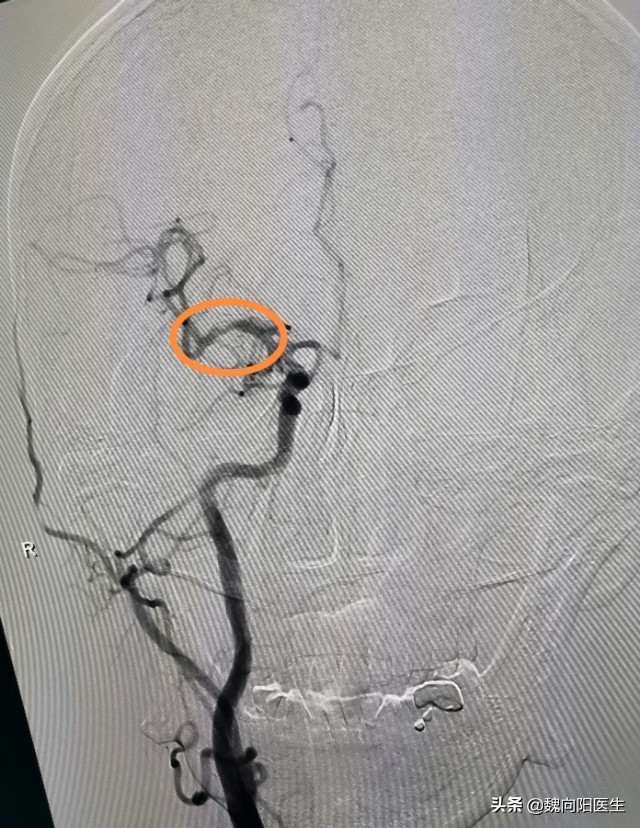

转入神经科之后,立即给安排的脑血管造影检查。

果然如医生所料,患者的脑血管确实存在大问题。脑血管造影提示:右侧大脑中动脉中度狭窄,且动脉斑块不规则。